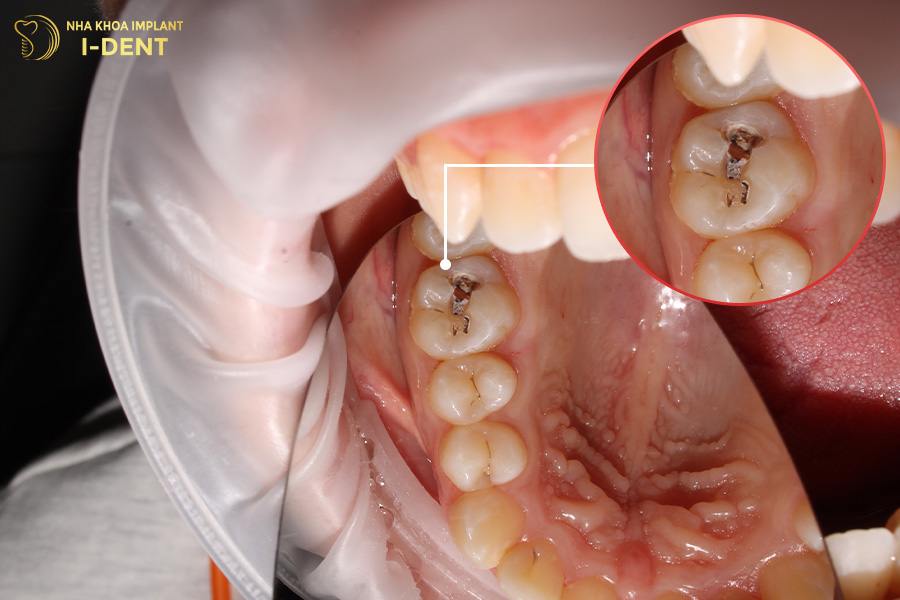

2.3 Sâu răng độ 3 ( Sâu đến tủy răng)

Trong các loại sâu răng thì mức độ sâu răng độ 3 được cảnh báo là nguy hiểm đến sức khoẻ nhất.

Khi bạn có thể cảm nhận những cơn đau nhức, thậm chí đau dữ dội lúc về đêm thì có nghĩa là tình trạng bệnh của bạn đã chuyển sang mức độ sâu răng nặng. Vi khuẩn sẽ ăn sâu vào vị trí đáy chân răng, hình thành ổ viêm nhiễm và gây ra tình trạng viêm tủy răng. Đây là nguyên nhân chính làm tăng nguy cơ áp xe răng, sâu răng hàm nặng, thậm chí là mất răng, nhiễm trùng máu.

Sâu răng độ 3 ( Sâu đến tủy răng).

Khi sâu răng đã diễn biến đến mức độ nghiêm trọng, bạn cần đến khoa để nha sĩ xử lý kịp thời. Nếu như chân răng chưa bị vi khuẩn tấn công đến, bác sĩ sẽ áp dụng phương án trám răng để phục hồi vết sâu. Còn nếu tủy răng đã bị phá huỷ nhiều thì bác sĩ sẽ chỉ định nhổ bỏ răng để tránh nhiễm trùng xương hàm.